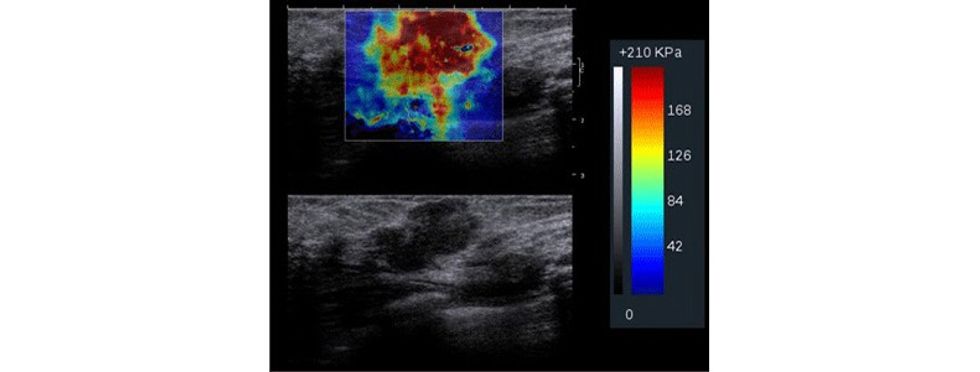

Të dhënat e fituara përpunohen përmes paketës softuerike në formë të color mapping apo grayscale për të vizualizuar zonën me interes e cila ekzaminohet.

Parimet bazë te elastografisë bazohen në dukurinë që indet nën kompresion shfaqin tendosje dhe kjo do të paraqitet me karakteristika të ndryshme. Prandaj, nën kompresion, në boshtin aksial, duke bërë matjet, mund të vlerësohet ngurtësia dhe elasticiteti i indit, para dhe pas kompresionit, ndërsa imazhi i paraqitur dhe i llogaritur quhet elastogram, ku fushat me ngurtësi të rritur dhe elasticitet të ulur paraqiten me ngjyrë të kaltër.

Indet paraqesin tendencë të ngurtësisë në ndërrimet malinje dhe imazhet rezultojnë me një kontrast me të rritur meqë kanë tendencë të ngurtësimit dhe fortësisë që rezulton me tendosje dhe ulje të elasticitetit nën kompresion të aplikuar.

Me aplikimin e elastografisë krahas ultrazërit konvencional, mundësohet që të rritet specificiteti i ultrazërit, sidomos në lezionet e kategorizuara me BiRads 4, duke bërë përcaktimin e elasticitetit të indit, detektim të qartë të nivelit të elasticitetit të indit dhe, marrë parasysh që formacionet me natyrë malinje kanë dendësi më të lartë dhe elasticitet të ulur gjatë aplikimit të kompresionit në boshtin aksial e shprehur në kPa. Pastaj me anë të mapingut qartë detektohet natyra e lezionit.

Përveç caktimit të natyrës së formacionit, me saktësi më të duhur mund të përcaktohen edhe dimensionet e formacionit duke detektuar më me saktësi ndryshimet në indet përreth, të cilat me metodën e ultrazërit konvencional, nuk mund të detektohen me saktësi.